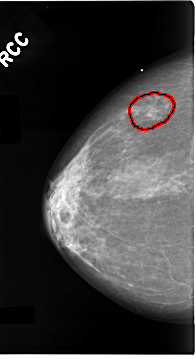

C_0096_1.RIGHT_CC

FILE: C_0096_1.RIGHT_CC.OVERLAY

TOTAL_ABNORMALITIES 1

ABNORMALITY 1

LESION_TYPE CALCIFICATION TYPE PLEOMORPHIC DISTRIBUTION CLUSTERED

LESION_TYPE MASS SHAPE IRREGULAR MARGINS ILL_DEFINED

ASSESSMENT 5

SUBTLETY 4

PATHOLOGY MALIGNANT

TOTAL_OUTLINES 1

BOUNDARY